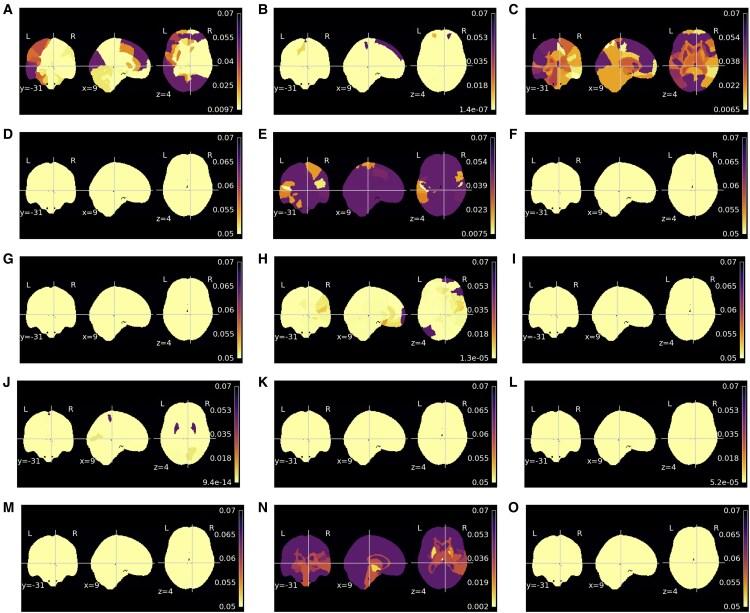

Brain age gap estimation (BrainAGE), the difference between predicted brain age and chronological age, might be a putative biomarker aiming to detect the transition from healthy to pathological brain ageing. The biomarker primarily models healthy ageing with machine learning models trained with structural magnetic resonance imaging (MRI) data. BrainAGE is expected to translate the deviations in neural ageing trajectory and has been shown to be increased in multiple pathologies, such as Alzheimer's disease (AD), schizophrenia and Type 2 diabetes (T2D). Thus, accelerated ageing seems to be a general feature of neuropathological processes. However, neurobiological constraints remain to be identified to provide specificity to this biomarker. Explainability might be the key to uncovering age predictions and understanding which brain regions lead to an elevated predicted age on a given pathology compared to healthy controls. This is highly relevant to understanding the similarities and differences in neurodegeneration in AD and T2D, which remains an outstanding biological question. Sensitivity maps explain models by computing the importance of each voxel on the final prediction, thereby contributing to the interpretability of deep learning approaches. This paper assesses whether sensitivity maps yield different results across three conditions related to pathological neural ageing: AD, schizophrenia and T2D. Five deep learning models were considered, each model trained with different MRI data types: minimally processed T-weighted brain scans, and corresponding grey matter, white matter, cerebrospinal fluid tissue segmentation and deformation fields (after spatial normalization). Our results revealed an increased BrainAGE in all pathologies, with a different mean, which is the smallest in schizophrenia; this is in line with the observation that neural loss is secondary in this early-onset condition. Importantly, our findings suggest that the sensitivity, indexing regional weights, for all models varies with age. A set of regions were shown to yield statistical differences across conditions. These sensitivity results suggest that mechanisms of neurodegeneration are quite distinct in AD and T2D. For further validation, the sensitivity and the morphometric maps were compared. The findings outlined a high congruence between the sensitivity and morphometry maps for age and clinical group conditions. Our evidence outlines that the biological explanation of model predictions is vital in adding specificity to the BrainAGE and understanding the pathophysiology of chronic conditions affecting the brain.

脑龄差距估计(BrainAGE),即预测脑龄与实际年龄之间的差异,可能是一种旨在检测从健康脑老化向病理性脑老化转变的潜在生物标志物。该生物标志物主要通过使用结构磁共振成像(MRI)数据训练的机器学习模型来模拟健康老化。BrainAGE有望转化神经老化轨迹中的偏差,并且已被证明在多种疾病中会增加,如阿尔茨海默病(AD)、精神分裂症和2型糖尿病(T2D)。因此,加速老化似乎是神经病理过程的一个普遍特征。然而,仍有待确定神经生物学限制因素,以便为该生物标志物提供特异性。可解释性可能是揭示年龄预测以及理解与健康对照相比,在特定病理情况下哪些脑区导致预测年龄升高的关键。这对于理解AD和T2D中神经退行性变的异同至关重要,这仍然是一个悬而未决的生物学问题。敏感性图通过计算每个体素对最终预测的重要性来解释模型,从而有助于深度学习方法的可解释性。本文评估了敏感性图在与病理性神经老化相关的三种情况下(AD、精神分裂症和T2D)是否会产生不同的结果。考虑了五个深度学习模型,每个模型使用不同的MRI数据类型进行训练:最少处理的T加权脑扫描,以及相应的灰质、白质、脑脊液组织分割和变形场(空间归一化后)。我们的结果显示,在所有疾病中BrainAGE均增加,但其平均值不同,在精神分裂症中最小;这与在这种早发性疾病中神经损失是次要的这一观察结果一致。重要的是,我们的研究结果表明,所有模型的敏感性(即区域权重指标)随年龄而变化。一组区域在不同情况下显示出统计学差异。这些敏感性结果表明,AD和T2D中的神经退行性变机制截然不同。为了进一步验证,比较了敏感性图和形态测量图。研究结果表明,年龄和临床组条件下的敏感性图与形态测量图高度一致。我们的证据表明,模型预测的生物学解释对于增强BrainAGE的特异性以及理解影响大脑的慢性疾病的病理生理学至关重要。